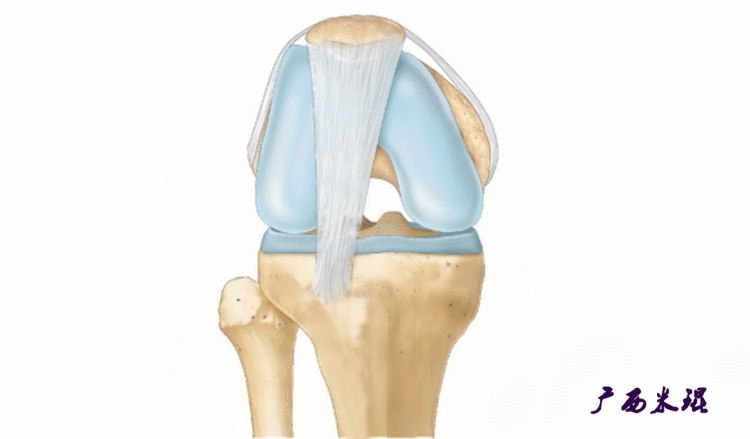

髌骨脱位绝大部分是向外侧脱位,脱位后,髌股关节内侧的稳定结构,包括髌股关节内侧支持带、股内侧肌、内侧髌股韧带均被撕裂,导致膝关节腔内积肿,在髌骨脱位以及自行复位的过程中,髌骨内侧面与股骨髁外侧面撞击,会引起软骨损伤或骨软骨骨折,所以,千万不要把髌骨脱位当作成一个简单的疾病。

(4)MPFL重建

从0到30°限制髌骨外侧位移最重要的是MPFL(内侧髌股韧带),文献报道认为导致髌股关节不稳的主要原因是内侧髌股韧带损伤,而在限制髌骨向外移位过程中,内侧髌股韧带提供约60%的力量,所以重建MPFL是治疗复发性髌骨脱位的有效方法。即使这样,MPFL重建也不是万能的,寄希望于MPFL重建解决所有的髌骨脱位肯定是不现实的,MPFL重建有着严格的适应症和技术要求,对于骨骺未闭合者,股骨端的骨隧道必须避开骺板,以免影响骨骼的生长。